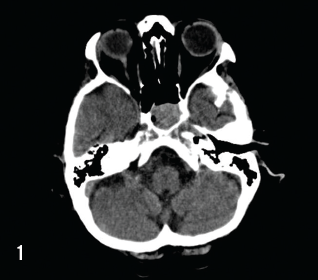

A 71-year-old female with a past medical history of hypertension presented to the emergency department with an 8-week history of neurological symptoms including confusion, short-term memory loss, and progressive weakness. Labwork revealed severe hypercalcemia (15.3 mg/dL [range: 8.5-10.5 mg/dL]), moderate anemia (hemoglobin levels at 9.5 g/dL [range: 11.5-15.5 g/dL]), and mild kidney insufficiency (creatinine levels at 1.47 mg/dL [range: 0.70-1.40 mg/dL]). An outpatient CT of the head revealed a mass within the sella turcica (Figure 1). She was consequently hospitalized for evaluation.

A skeletal survey revealed innumerable small lytic lesions throughout the skeleton, most prominent within the skull. A bone marrow biopsy was performed and demonstrated findings consistent with kappa chain multiple myeloma. Given the presence of a suprasellar mass, pituitary function was assessed and no significant abnormalities were found. Transsphenoidal biopsy of the sphenoid mass was performed; the pathology report revealed neoplastic cells strongly positive with antibodies to CD138 and kappa light chains, consistent with plasma cell neoplasm (Figure 2). She was consequently diagnosed with multiple myeloma.

The patient underwent treatment of her multiple myeloma with melphalan, bortezumab, and prednisone. Follow-up CT of the head demonstrated absence of the suprasellar mass following chemotherapy.